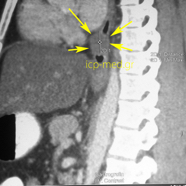

Images 6-8: Leiomyoma of the oesophagus (esophagus) measuring 5.5 x 3 x 2.5 cm in a 42-yo male smoker